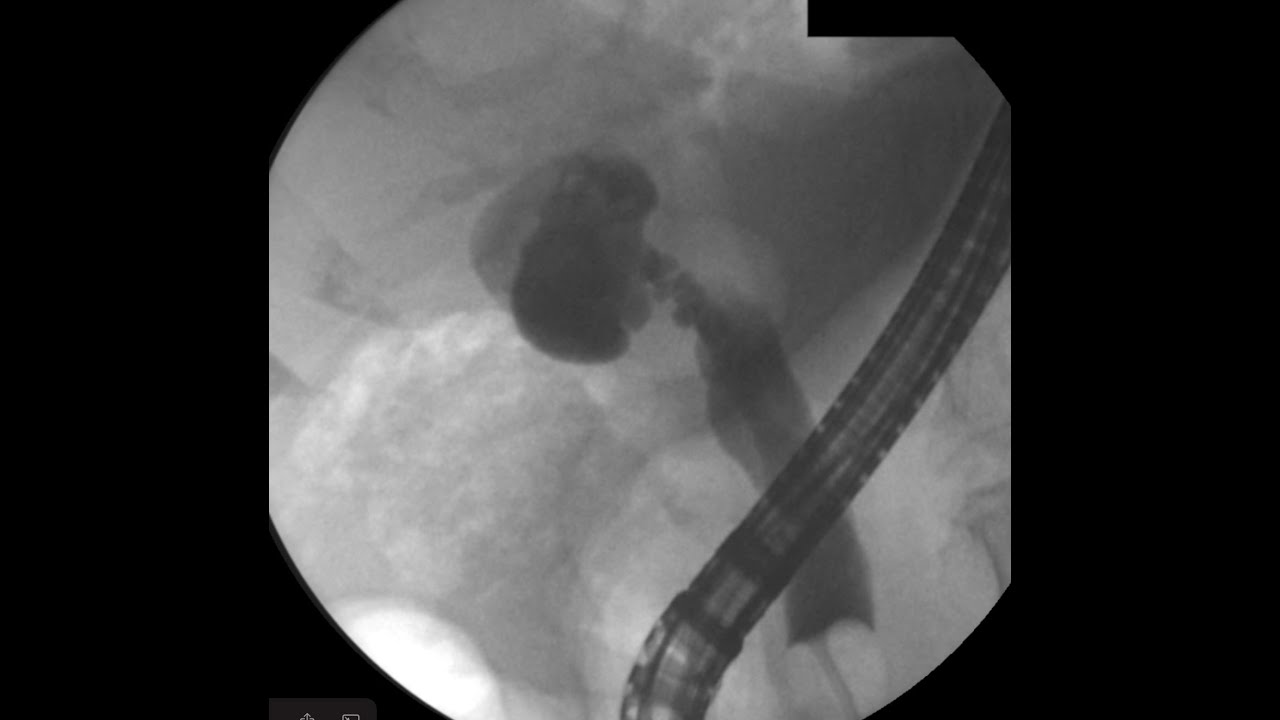

EUS guided GB drainage in nondistended gallbladder YouTube Flushing Gallbladder Tube A cholecystostomy is a procedure to place a drain into your gallbladder. Healthcare providers place a catheter (tube) through a percutaneous cholecystostomy to drain fluid from your gallbladder and relieve pressure,. Apply soap rub them together thoroughly for 15 seconds. Find out how to prepare, what to expect, and how to. Caring for your percutaneous cholecystostomy drain after placement is. Flushing Gallbladder Tube.